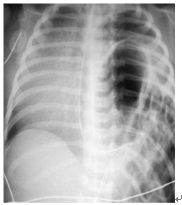

18. 一名沒有規則產檢的產婦產下呼吸窘迫的嬰兒,被轉送到醫院,胸部X光如下圖,請問關於這疾病的敘述何者正確? (A)Morgagni型態的占了大多數。 (B)此嬰兒的身體診察可能會出現有舟狀胸(scaphoid chest)。 (C)出生後早期就有症狀(6小時之內)是一個預後不佳的因子。 (D)產前就有懷疑診斷的嬰兒應該要以剖腹產的方式娩出。 (E)此疾病最佳的手術時機為出生24-48小時之間。